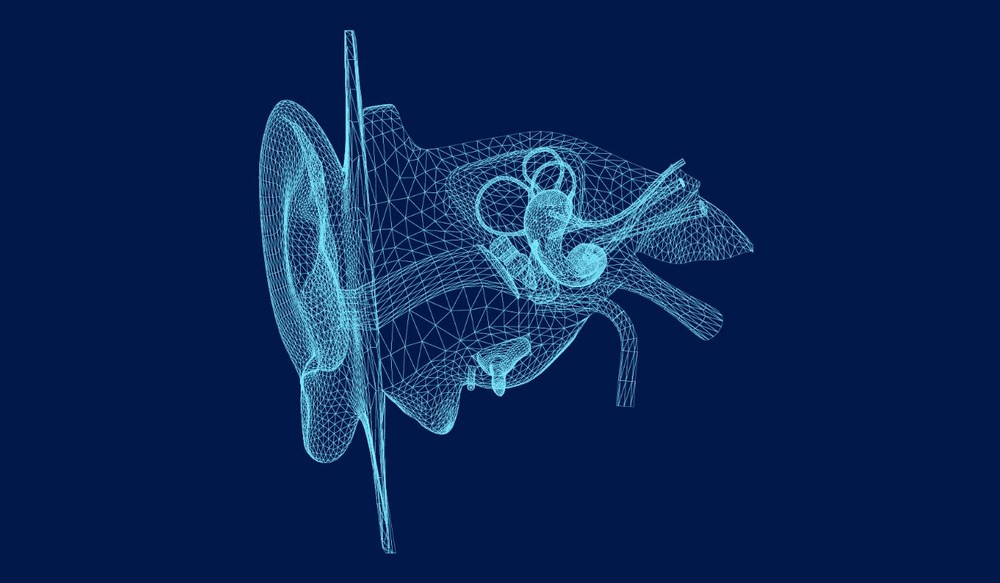

The ear plays an important role in helping us understand and interact with the sounds around us. It has three main sections: the outer ear, middle ear and inner ear. The outer ear collects sound waves and directs them through the ear canal to the eardrum. These sound waves cause the eardrum to vibrate, and those vibrations are passed through three small bones in the middle ear –the malleus, incus and stapes. These bones amplify the sound and transfer it to the inner ear for further processing.

In the inner ear, the cochlea converts these vibrations into electrical signals. Tiny hair cells inside the cochlea are responsible for detecting the vibrations and sending the signals to the brain through the auditory nerve. The brain then interprets these signals, turning them into recognizable sounds like voices or environmental noises. The inner ear is also responsible for balance, as the vestibular system tracks motion and helps us maintain stability.

Hearing and balance are connected through the intricate workings of the inner ear. While the cochlea is responsible for processing sounds, the vestibular system manages balance and spatial orientation. These two systems are housed close together within the inner ear and share some of the same structures. The vestibular system includes fluid-filled canals and small sensory structures that detect movement and changes in head position. These signals are sent to the brain, allowing us to adjust and maintain our balance as we move.